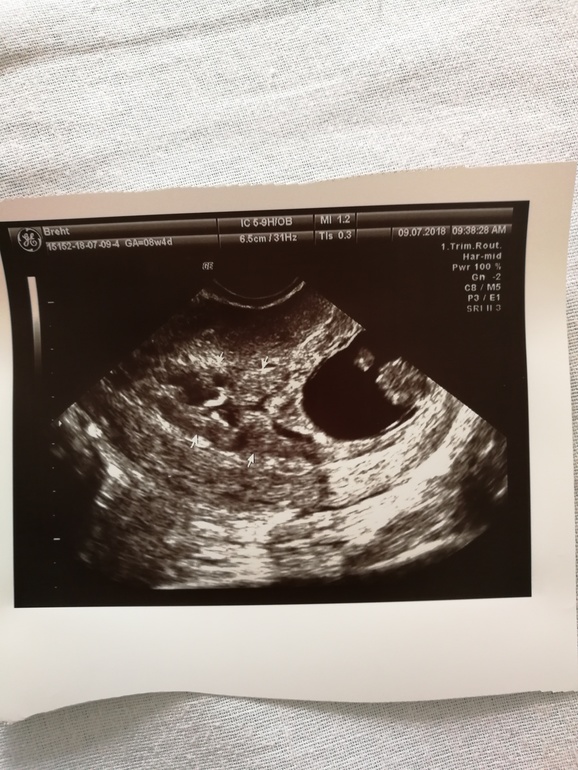

8 недель. Стационар.

6 июля положили в больницу с угрозой, ставят уколы с папаверином, берут постоянно кровь и мочу. Устала от этого режима и хочу домой. Сегодня делали узи, причём делал тот врач, который меня домой отправил в 4 недели, когда обращалась с болью. Нашли старую гематому, когда она появилась, интересно. Малыш мой растёт, ктр 18 мм, чсс 185, прикрепился по задней стенке, а это значит есть надежда на небольшой живот и меньшее количество растяжек🤞и на ранние шевелюшки. Дочку почувствовала в 16 недель. Завтра опять кровь и новое назначение лечения. Хоть бы не добавили уколы, попа болит, сидеть уже больно.